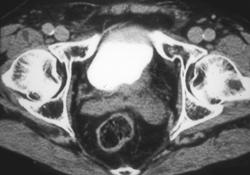

Healing Left Renal Abscess